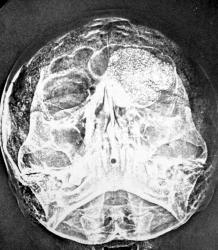

Беспокоили головные боли, несколько лет, легкий экзофтальм слева. От всех "оперативных" действий медиков категорически отказалась. Осталась единственная ЭРГ

Здравствуйте Валентин Львович! На другой стороне есть что то подобное, правда чуть выше. Но здесь был легкий экзофтальм... А ЭРГа веки отображала запросто.

Интересно услышать мнение коллег, по поводу линий просветления, помеченных стрелками.

Да, на элетрорентгенограммах, отражалось много чего "мягкотканного".

Каламбур - "Электрорентгенография - это МРТ "Доэмртешного периода".